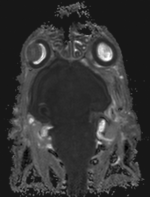

MRI baseline lleft MRI follow-up

fixed image 1/target

MRI mouse 1

moving image

MRI mouse 2